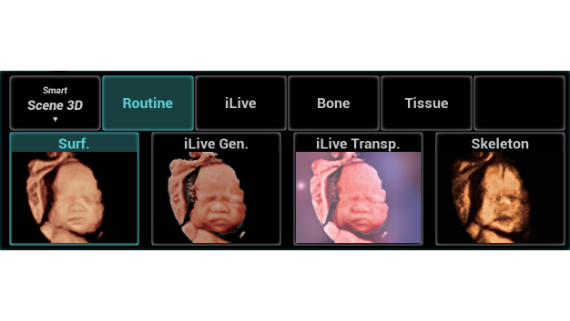

Gambar Klinis